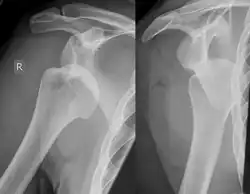

Diagnosis can be suspected by history and physical examination which is usually followed by imaging. Because of the mechanism of injury, apprehension of anterior dislocation is common with provocative maneuvers. Hill–Sachs lesions have been classified as "engaging" or "non-engaging", with engaging lesions defined by the ability of the glenoid to sublux into the humeral head defect during abduction and external rotation. Engaging dislocations have a higher risk of recurrent anterior dislocation, and their presence can help guide surgical management.[2] Imaging diagnosis conventionally begins with plain film radiography. Generally, anteroposterior (AP) radiographs of the shoulder with the arm in internal rotation offer the best yield while axillary views and AP radiographs with external rotation tend to obscure the defect. However, pain and tenderness in the injured joint make appropriate positioning difficult and in a recent study of plain film x-ray for Hill–Sachs lesions, the sensitivity was only about 20%. i.e. the finding was not visible on plain film x-ray about 80% of the time.[3]